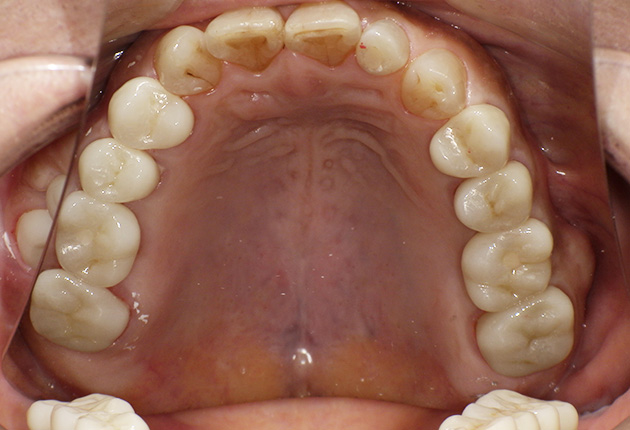

90分の治療で銀歯の状態からキレイな状態になります。噛み合わせの調整や審美面も使用しながら合わせます。

良く噛めて安心と、ご満足いただき大変嬉しく思います。笑顔も一層素敵になりました。

| 治療内容 | 欠損部インプラント 不正咬合に対し不良補綴のやり直しと合わせて咬合再構築 |

| 治療期間 | 4ヶ月 |

| 費用 | 200万円 |